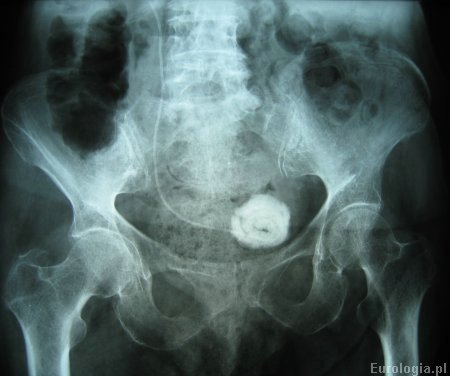

Fot. Kalcyfikacja cewnika DJ - złóg średnicy 5 cm na końcu pęcherzowym cewnika.

Fot. RTG przeglądowe nerek i pęcherza moczowego z widocznym cewnikiem DJ w prawym moczowodzie i kamieniem moczowym na końcu pęcherzowym cewnika.